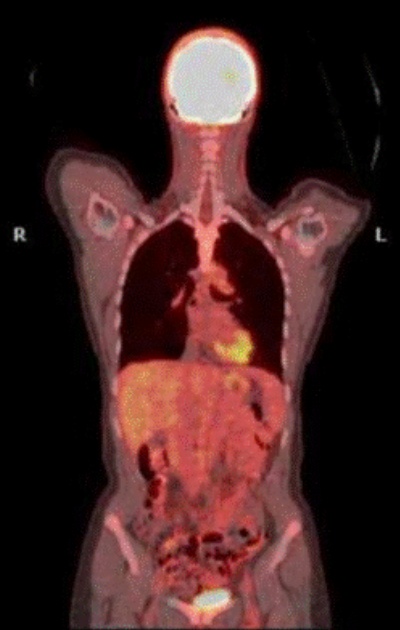

Meningkatkan Deteksi Kanker dengan Digital PET CT Scan

Health - 29 April 2025